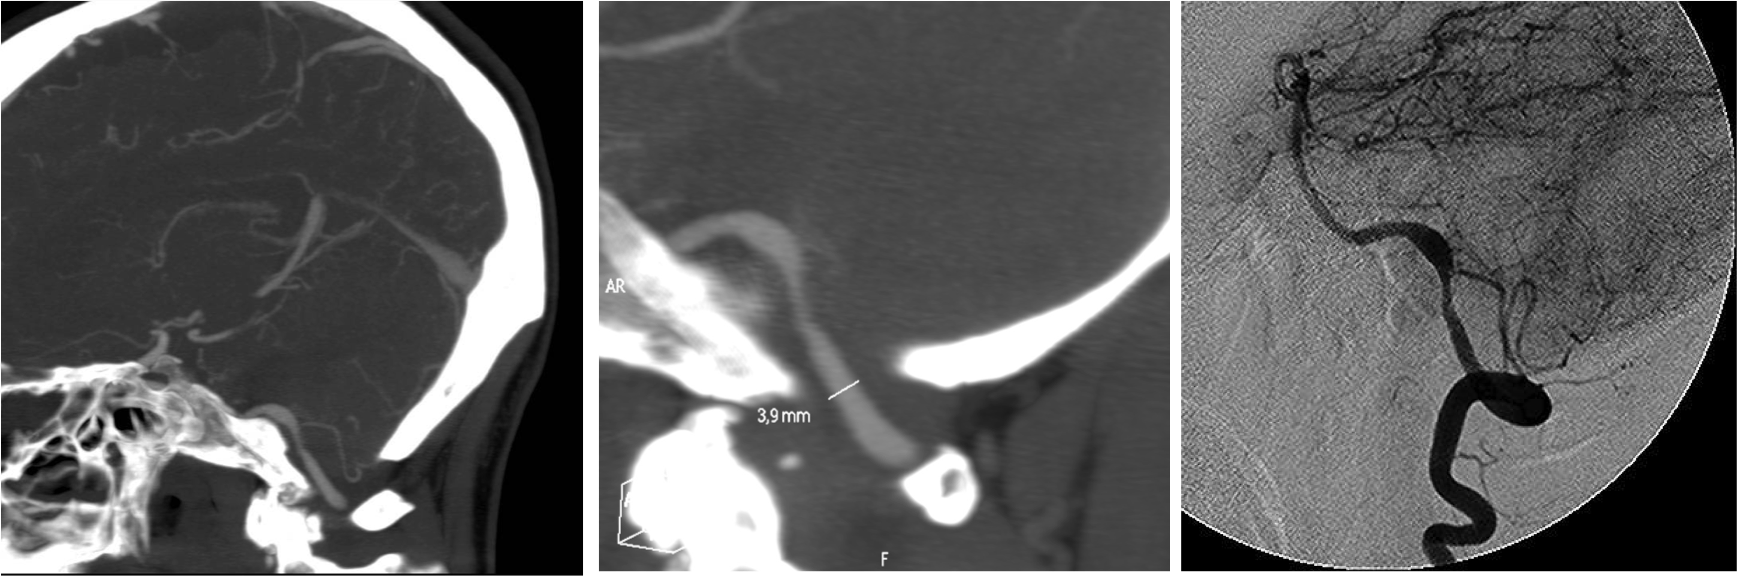

TC DE PERFUSIÓN.

Realizaremos un TC de perfusión fundamentalmente en estos dos supuestos:

- Cronología incierta.

- Ictus del despertar.

- Dudas diagnósticas.

El fundamento de la prueba consiste en administrar constraste iv y estudiar el primer paso de éste a través de la circulación cerebral (50 mL de cc; 4 mL/seg) a baja radiación (80 kVp; 150 mA). Se realiza un bloque de estudio de 4 cm a nivel de los ganglios basales (ya que a ese nivel encontramos los territorios de las ACA, ACM y ACP) y se aprovecha que el contraste pasa a través de la circulación cerebral produciendo hiperatenuación de los vasos, lo cual vamos a aprovechar para colocar un ROI arterial y otro ROI venoso que nos darán dos curvas de tiempo-atenuación de contraste

PASO 1º: COLOCAR LA LINEA MEDIA.

PASO 2º: DEFINIR VASOS. Colocación de los ROI.

- El ROI arterial debe seleccionarse en un arteria sana, preferiblemente en las ACA o en la ACM contralateral al lado infartado.

- El ROI venoso puede aplicarse por ejemplo en el seno venoso sagital superior o en la prensa de Herófilo.

PASO 3: MAPAS DE PERFUSIÓN

Tras la colocación de los ROI, se generan unos gráficos que deben estudiarse y verificar que:

- Las curvas deben tener un aplanamiento inical, luego un pico y finalmente un descenso = Indica que el contrasta ha pasado durante un tiempo adecuado.

- La curva venosa (azul) debe situarse más alto y con 1-2 segundos de retraso con respecto a la curva arterial (rojo). Este hecho indica una correcta entrada y salida del contraste.

Tras aplicar los ROI, el software de la estación de trabajo nos va a dar un mapa de la perfusión en forma de colorines codificados que nos van a aportar tres parámetros fundamentales (sacados de ecuaciones matemáticas,se denomina Deconvolución).

- Tiempo de tránsito medio (TTM): indica áreas isquémicas (puede sobreestimar un poco el tejido de verdad en peligro).

- Flujo sanguíneo cerebral (CBF): indica el área de isquemia crítica (es más específica que el TTM).

- Volumen sanguíneo cerebral (CBV): indica el área de necrosis ya instaurada.

El mapa del TTM debería ser el primero en analizarse ya que muestra las anomalías más groseras. Lo comparamos con un ROI con el parénquima contraleral normal y si está aumentado en la zona de sospecha diagnóstica, indica isquemia.

A continuación se estudian los mapas de CBF y CBV, los cuales son más específicos para distinguir la isquemia del infarto. La disminución del CBF indica zona de isquemia crítica, mientras que la disminución del CBV indica zona de necrosis ya instaurada. Esta es la diferencia.

Conceptos a tener claro:

- Hay un concepto llamado Mismatch que significa discordancia y que refleja precisamente esta diferencia anteriormente explicada. No concuerdan las áreas afectadas de isquemia y con las áreas ya necrosadas. Es equivalente a decir que de todo el territorio afectado por la isquemia (indicada por el TTM y CBF) hay una zona que ya se ha muerto del todo y no se va a recuperar (inidicada por el CBV). Cuando el mismatch es mayor del 20% hay que tratar al paciente.

- Penumbra = Tejido afectado/aturdido = Aumento de TTM ; Diminución del CBF ; Normal el CBV

- Core = Tejido necrótico = área afectada en el volumen = Aumento del TTM; Disminución del CBF; Disminución del CBV.

- Tejido salvable = TTM – CBV.